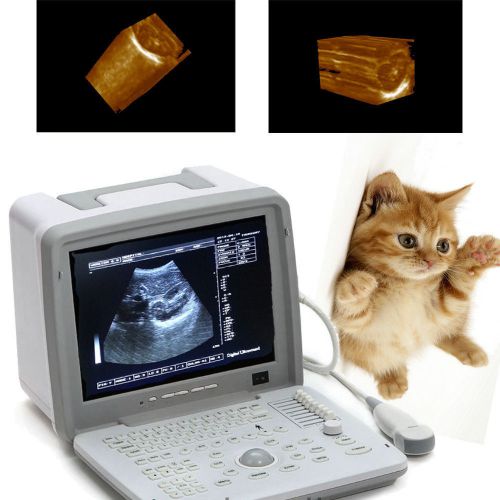

Brand | Denshine |

| Screen | 12-inch SVGA high resolution monitor | ||

| technology | Full digital imaging technology | ||

| Probes optional | convex linear transvaginal rectal | ||

| probe connectors | two | ||

| Approved | CE FDA | ||

| 3D | 3D Ultrasound image working station |

Veterinary VET 3D Full Digital Portable Ultrasound Scanner convex 3D workstation